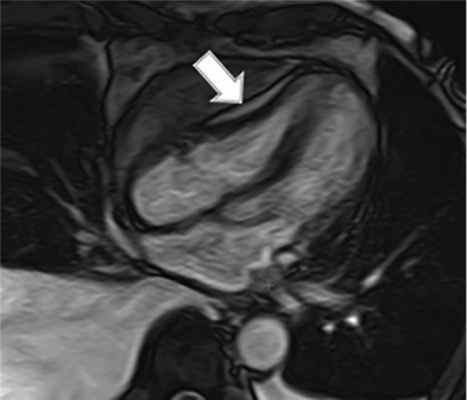

С учетом имеющихся у пациента признаков застоя по большому кругу кровообращения (отеки, двусторонний плевральный выпот, больше выраженный справа, асцит), неоднородного утолщения листков перикарда по данным КТ при отсутствии легочной гипертензии и систолической дисфункции левого желудочка было высказано предположение о наличии констриктивного перикардита. Дополнительно выполнена МРТ сердца (рис. 2), подтверждено утолщение перикарда.

Рис. 2. МРТ сердца, четырехкамерная плоскость. Отмечается утолщение перикарда (указано стрелкой).